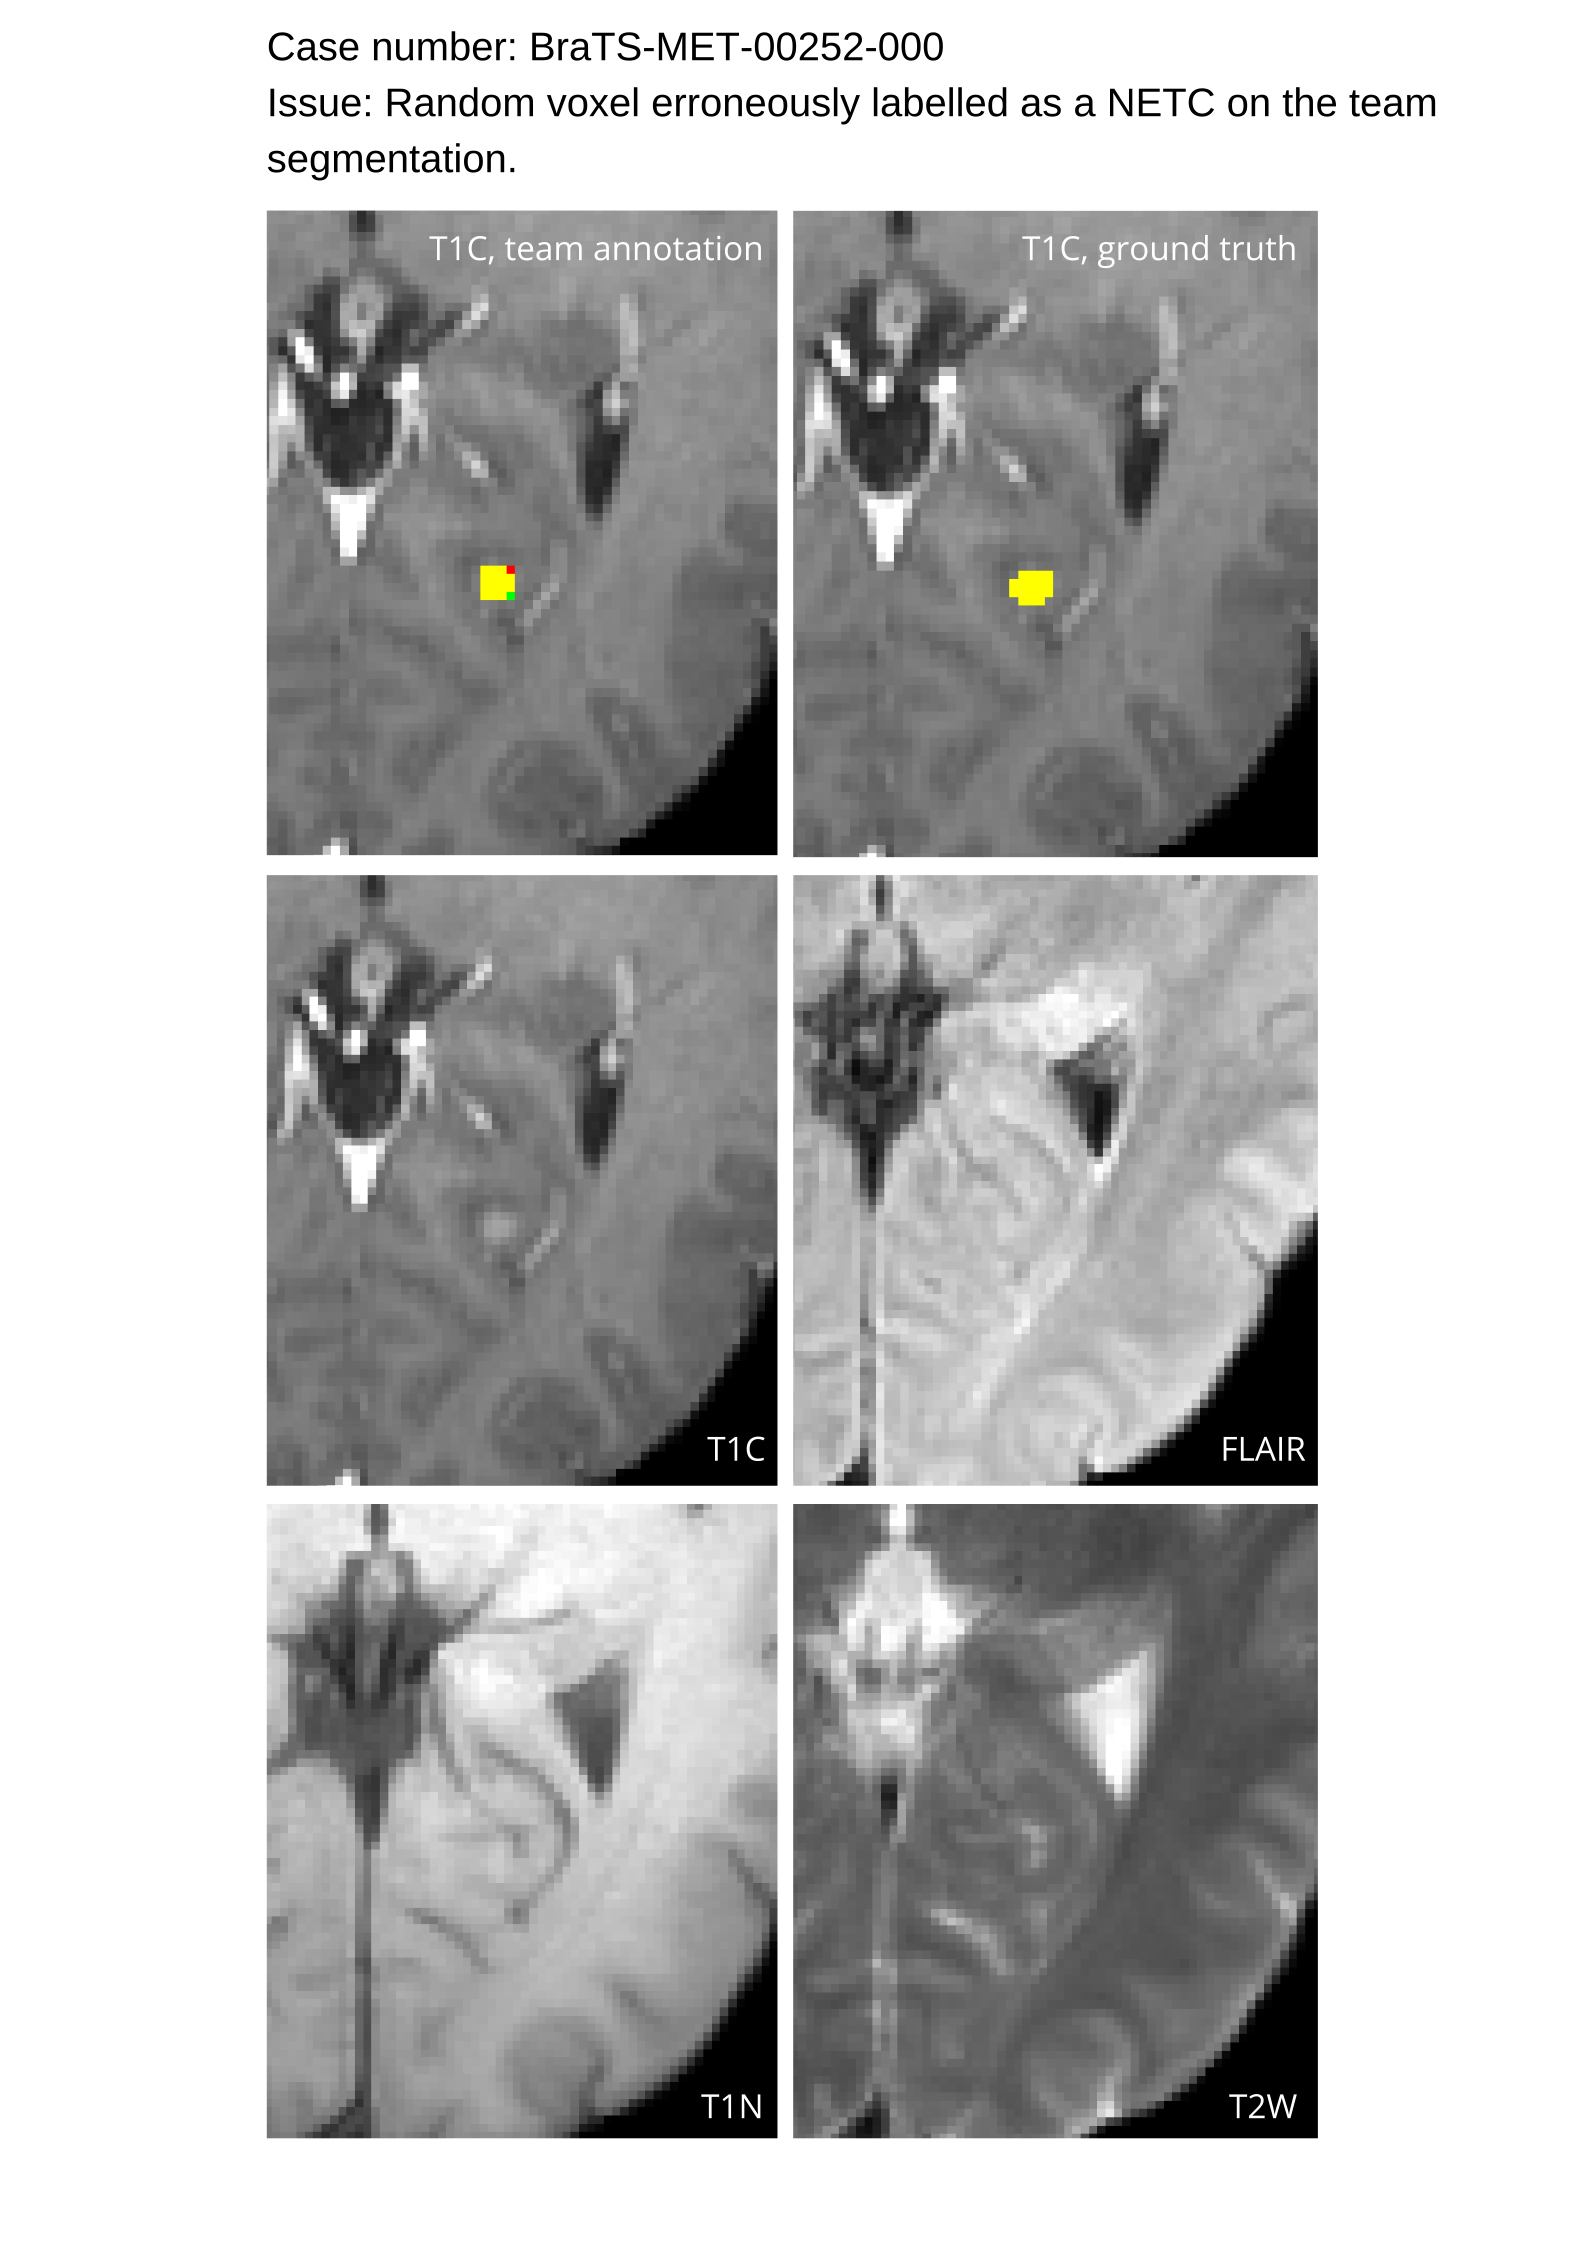

Approvers reviewed the volunteer annotations and either approved the case or returned it to students for re-annotation. Additionally, a QC process was implemented, which included removing all random voxels and any voxels outside the brain mask, ensuring all images had the same parameters (space, orientation, and origin) as the SRI24 atlas, and verifying the presence of all segmentations and segmentation masks are in the folder with original NIfTI images.